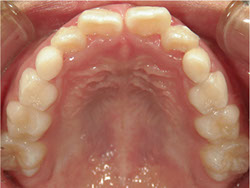

1期治療でスケルトンタイプの拡大装置で歯列拡大後、歯も抜かずにきれいになりました。

矯正前

矯正中

矯正終了後